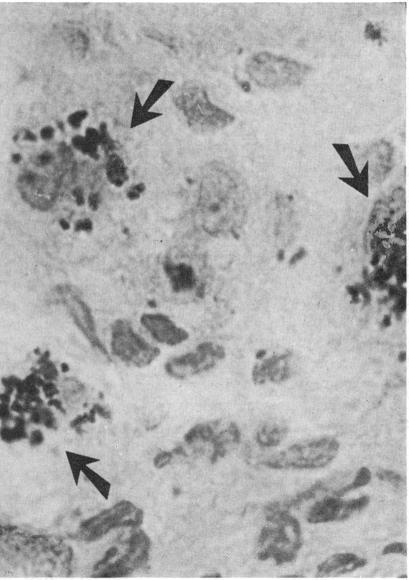

Liver biopsies from eight patients with primary biliary cirrhosis, two with chronic active hepatitis of a cholestatic form, three with long-standing alcoholic liver cirrhosis, and one with extrahepatic biliary obstruction were studied. In each case dark brown cytoplasmic material was seen after staining of the tissue sections with Shikata's orcein method. In exactly the same cellular and subcellular locations as the orcein-positive material, and with morphologically equal granules, two different ordinary staining methods for copper (rubeanic acid and Mallory-Parker's haematoxylin) gave positive reactions. The earlier histochemical findings have revealed the protein nature and high sulphydryl content of the orcein-positive material. Its close association with copper in liver sections suggests its copper-binding nature and indicates that a common copper-protein complex accumulates in the cytoplasm of liver cells during longstanding cholestasis in biliary diseases of various pathogenetic origin.

对8例原发性胆汁性肝硬化患者、2例胆汁淤积型慢性活动性肝炎患者、3例长期酒精性肝硬化患者和1例肝外胆管梗阻患者的肝脏活检组织进行了研究。在每例患者中,用志方氏orcein法对组织切片染色后,可见深棕色细胞质物质。在与orcein阳性物质完全相同的细胞和亚细胞位置,以及形态相同的颗粒,两种不同的铜常规染色方法(二硫代氨基甲酸盐和马洛里-帕克苏木精)均呈阳性反应。早期的组织化学研究结果揭示了orcein阳性物质的蛋白质性质和高巯基含量。它在肝脏切片中与铜的密切关联表明其具有铜结合性质,并表明在各种致病原因引起的胆汁性疾病的长期胆汁淤积过程中,一种常见的铜蛋白复合物在肝细胞的细胞质中积累。